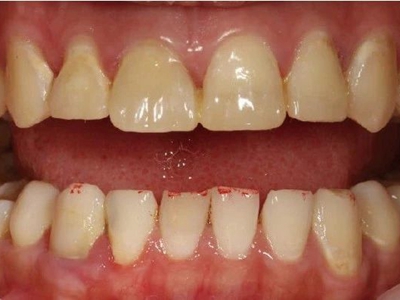

酸蚀症牙齿缺损不平整图

酸蚀症患者的牙齿会发生缺损,轻度时仅表现为牙齿尖端凹凸不平,有少量骨质缺失,缺损处有黄褐色至红褐色斑点,该病可能是长期接触外源性酸性物质而致病。